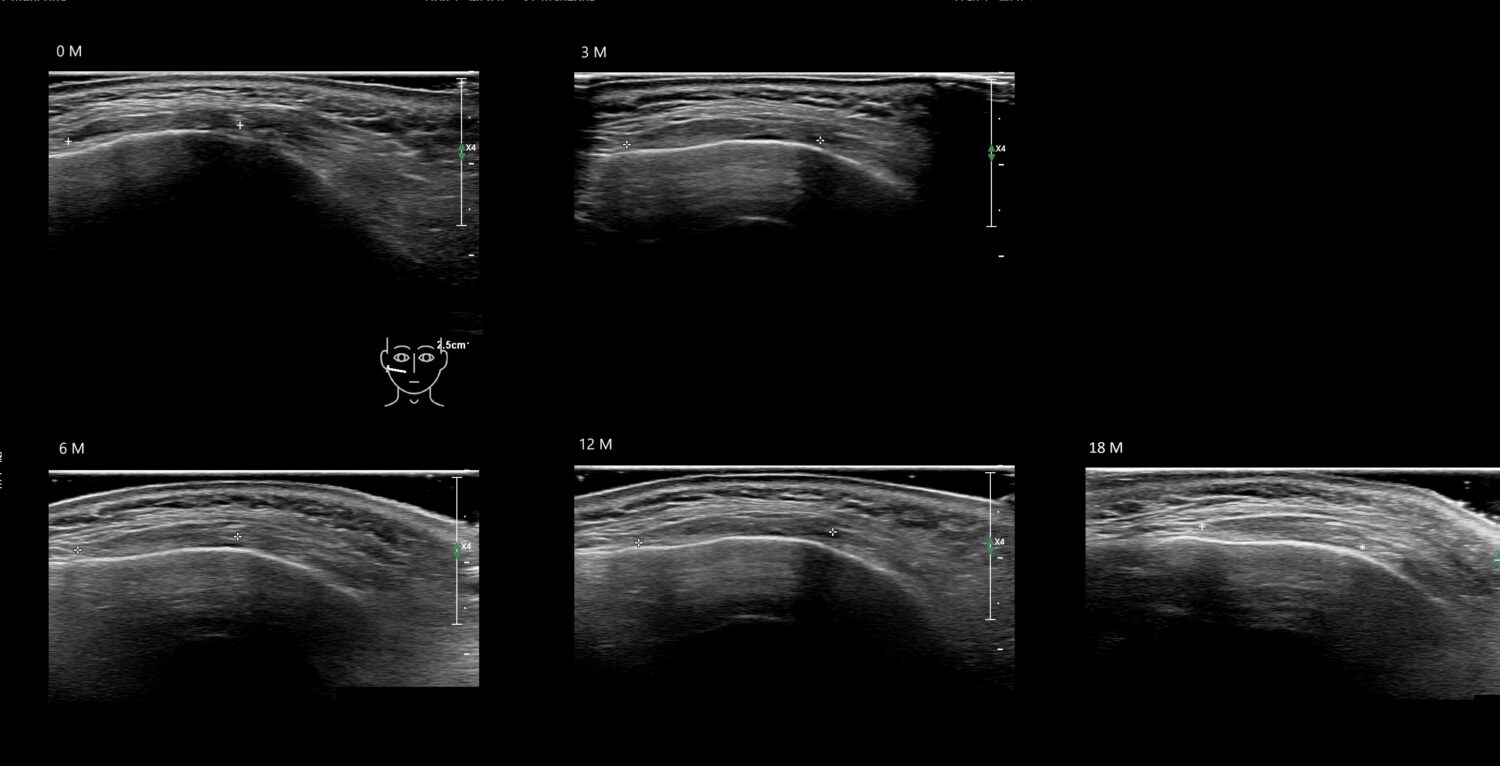

Fillers

Draw in the image on the right where the fillers are located. To check if your answer is correct, please click on the secondary image.